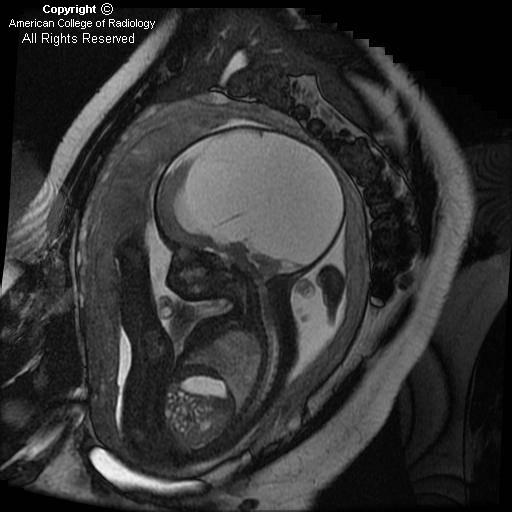

Fetal hydrocephalus

Findings

The cerebellar hemispheres (Figure 1), vermis and cisterna magna (Figure 1) are normal.

There is hydrocephalus, manifested by the marked dilatation of lateral ventricles, a midline falx (Figure 2 and Figure 3), and thinning of the cerebral cortical mantle (Figure 2 and Figure 3).

The fourth ventricle (Figure 4) is normal, therefore, the obstruction is suspected to be at the level of the Acqueduct of Sylvius (Figure 4). No obstructing lesions are identified.

Aqueductal Stenosis is more common in males as seen in this case (Figure 5)